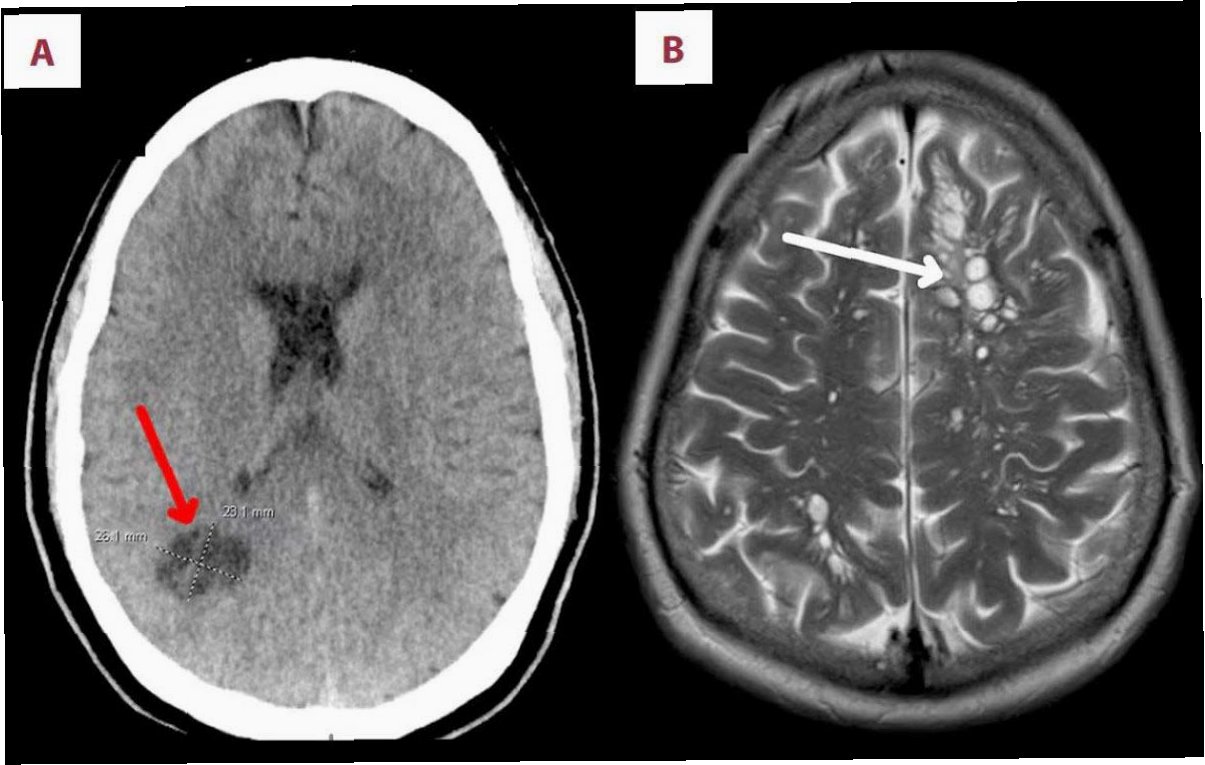

환자는 여러 검사에도 불구하고 기생충 감염의 명확한 흔적을 찾기 어려웠습니다. 세균, 곰팡이, 기생충 항체 검사 등에서 음성 반응이 나왔고, 구충제 처방에도 호흡기 증상이 쉽게 가라앉지 않았습니다. 수개월간 증상이 지속되면서 환자는 우울감과 기억상실까지 겪게 되었습니다. 결국 뇌 MRI 검사를 통해 우측 전두엽에서 병변이 발견되었고, 뇌 조직 검사 결과 살아있는 기생충이 확인되었습니다. 의료진은 뇌 조직에서 약 80mm 길이의 기생충을 제거하는 수술을 시행했습니다.